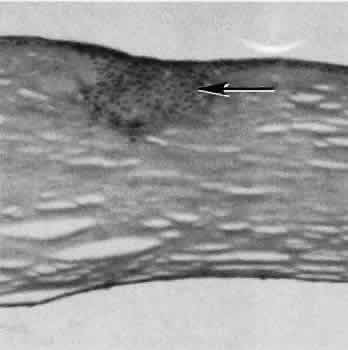

Fig. 11. Light micrograph of a small rent in the capsule of a crystalline lens caused by a needle tip. A small wound such as this may heal leaving only focal opacification. Generalized lens opacification is the more common outcome of crystalline lens capsular damage. (Periodic acid-Schiff stain; × 100.)